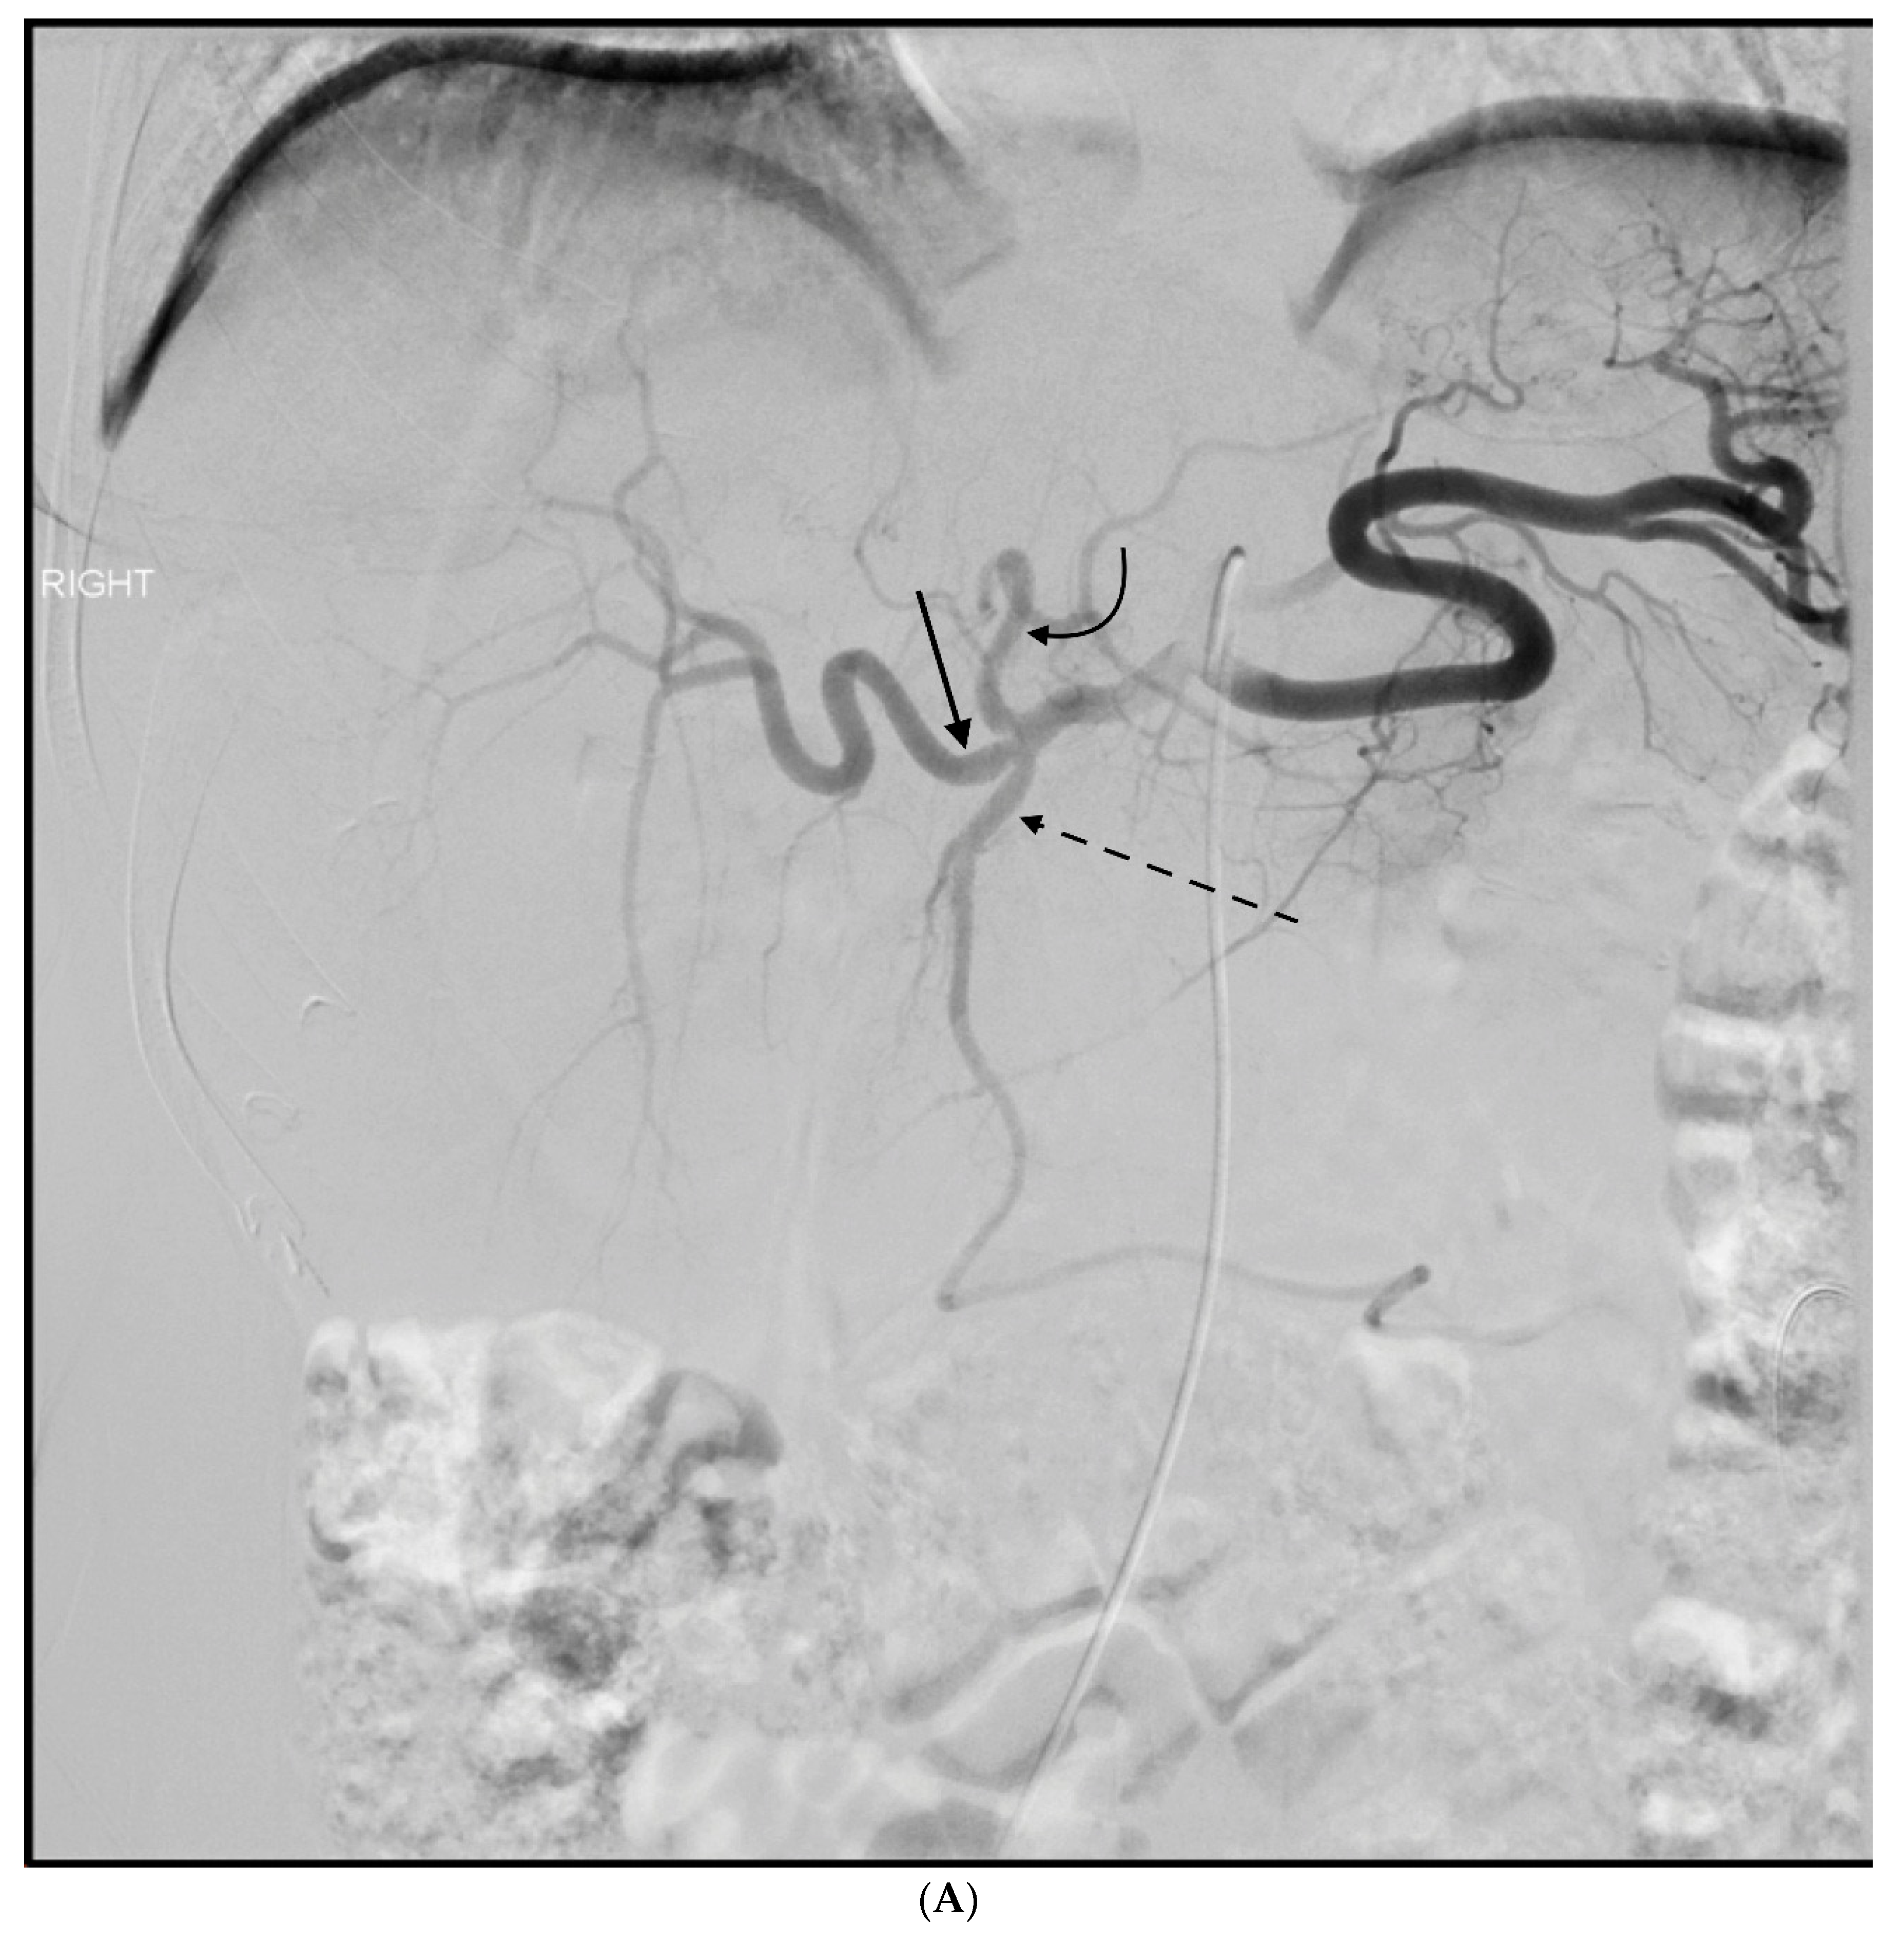

3. GDA Embolization in Gastrointestinal Bleeding

- Anil, G.; Tan, A.G.; Cheong, H.W.; Ng, K.S.; Teoh, W.C. Emergency gastroduodenal artery embolization by sandwich technique for angiographically obvious and oblivious, endotherapy failed bleeding duodenal ulcers. Clin. Radiol. 2012, 67, 468–475. [Google Scholar] [CrossRef] [PubMed]